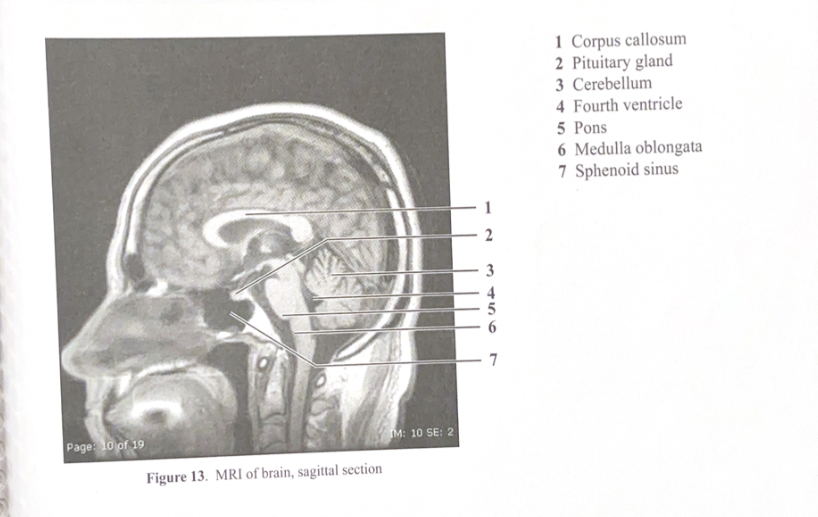

Figure 13. MRI of brain, sagittal sectionÂ

Corpus callosumÂ

Pituitary glandÂ

CerebellumÂ

Fourth ventricleÂ

PonsÂ

Medulla oblongataÂ

Sphenoid sinusÂ